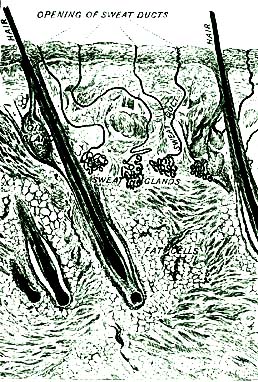

6. Our hands and face and the whole body are covered with something as soft and smooth as the finest silk. It is the skin. What is it that grows from the skin on the head? and what at the ends of the fingers and the toes? We shall learn more about the skin, the hair, and the nails in another lesson.

6. The whole body is covered by the skin.

4. Still another use for water is to dissolve and wash out of our bodies, through the sweat of the skin, and in other ways, the waste and worn-out particles which are no longer of any use.

6. It is best not to drink iced water when the body is heated, or during meals. If it is necessary to drink very cold water, the bad effects may be avoided by sipping it very slowly.